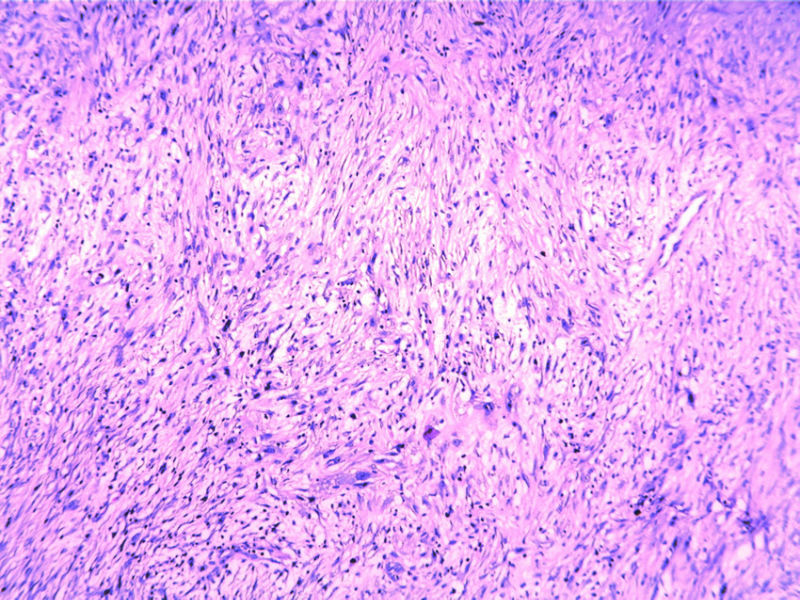

瞧这个小腿肿物,再看IHC(48Y,V2X1X1cm)

• 瞧这个小腿肿物,再看IHC(48Y,V2X1X1cm)图3

图3

病人20年前小腿外伤骨折,一直未能愈合,长啊长......

P63+、CD34仅血管阳性、CK+

梭性细胞鳞癌?基本排除了上皮样肉瘤,虽然病史和形态也可以是上皮样肉瘤。确实很难想到!楼主是刚开始就把这个排在第一诊断的位置吗?

好病例,皮肤梭形细胞鳞癌少见,应该能够找见典型鳞癌的区域吧。

梭形细胞CK阳性,炎性肌纤维母可以出现,20年病程虽可以排除,但是他毕竟是骨折未愈的创口;取材部位深的滑膜肿也不能完全排除,标记还得加做